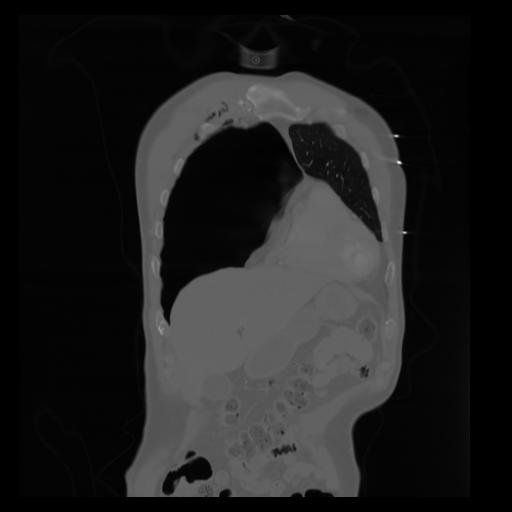

29 CUERPO,CE,Coronal,3.000,CUERPO,Coronal,